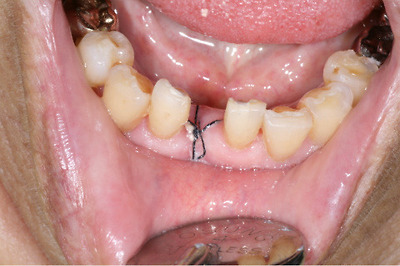

Pack을 해놨는데 열어보니까 이식해 놓은게 마치 딱지처럼 너덜해져 있더군요 ㅜㅜ

그나마 이식전 수여부의 V자 홈을 하이스피드로 맨들하게 갈아놔서 보철은 그냥 해도

될거같네요... 아마도 쫄아서 하이스피드로 너무 표면만 살짝 갈고 붙인게 원인이지 않나 생각됩니다...